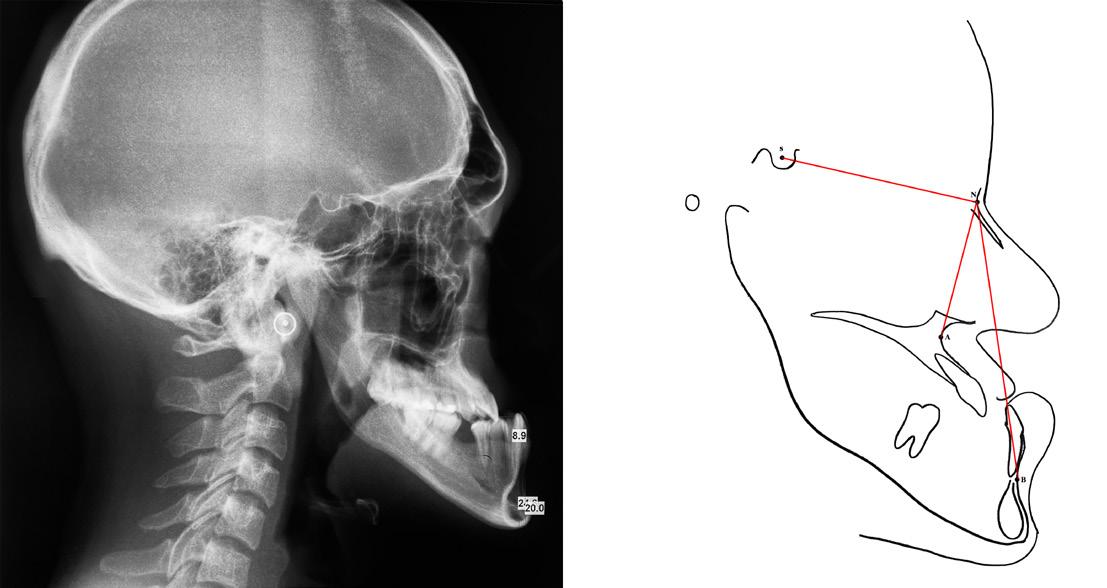

Identified subjects underwent comprehensive clinical examination by one of the researchers at IIUM Specialist Clinic to ensure no anomalies in tooth number, morphology and eruption. A lateral cephalometric radiograph was taken as a record for cephalometric analysis. Eastman analysis,12 measuring sellanasion-A-point angle (SNA), sella-nasion-B point angle (SNB), A point-nasion-B point (ANB) and the Wits appraisal (AoBo) were executed.13 The points as illustrates in Figure 1.

SNA angle was used to assess the position of maxilla to cranial base whilst SNB angle was used to determine the position of mandible to the cranial base. The ANB angle, which has been recognized as the most commonly used antero-posterior skeletal

Figure 1: Reference points on the cephalometric radiograph: Sella (S)midpoint of the sella turcica, Nasion (N), A point (A)- deepest point of concavity on the anterior profile of the maxilla, B point (B)- deepest point of concavity on the anterior surface of the mandibular symphysis, Gonion (Go)- the most posterior, inferior point on the angle of the mandible, Menton (Me)- the most inferior point on the mandibular symphysis, Pogonion (Pog)- the most anterior point of the mandibular symphysis, Porion (Po)- the upper midpoint of the external auditory meatus, Anterior nasal spine (ANS), Posterior Nasal Spine (PNS). (Figure reprinted with permission from Siva Dharma D, Abu Bakar N, Mustafa BE. Evaluation of Salivary Leptin Levels and Its Correlation with Class I, Class II, and Class III Facial Skeletal Pattern: A Prefatory Study. European Journal of Dentistry. Published online August 24, 2021. doi:https://doi. org/10.1055/s-0041-1727552)

discrepancy indicator14 was then calculated. It compares the relationship of the maxilla and the mandible with regards to the cranial base. The classification used denotes that a 2-4 degree value indicates a class I malocclusion, above 4 degrees indicates a Class II malocclusion and below 2 degrees is indication for a Class III malocclusion.15

The Wits appraisal, which compares the relationship of the maxilla and the mandible with regards to the functional occlusal plane was used to further confirm the antero-posterior occlusal disharmony. A line is drawn between the cusp tips of the molars and premolars and this is known as the functional occlusal plane (FOP). A perpendicular line is drawn from point A and point B to the FOP to give points AO and BO. The distance between AO and BO is measured. The average (Class I malocclusion) values are −1 mm (± 1.9 mm) for males and 0 mm (± 1.77 mm) for females.15

Values below the average values denote a Class II malocclusion and values above the average denote a Class III malocclusion.

Subjects were grouped into facial classes based on the analysis criteria below:

Cephalometric analysis criteria for Class I facial skeletal pattern:

1. Cephalometric value indicative of Class I based on Eastman (ANB within 2°to 4°, SNA within range of 81°±3° and SNB within range of 78°±3°) as shown in Figure 2.

2. Wits appraisal (AoBo) within Class I (- 2mm to +2mm)

3. Straight facial profile

tracing (right) of a Class I lateral cephalometric radiograph (left). To calculate angles SNA and SNB, lines are drawn between the points S, N, and A. The ANB angle is obtained by deducting angle of SNB from SNA. (Figure reprinted with permission from Siva Dharma D, Abu Bakar N, Mustafa BE. Evaluation of Salivary Leptin Levels and Its Correlation with Class I, Class II, and Class III Facial Skeletal Pattern: A Prefatory Study. European Journal of Dentistry. Published online August 24, 2021. doi:https://doi.org/10.1055/s-0041-1727552)

Cephalometric analysis criteria for Class II facial skeletal pattern:

• Cephalometric analysis with value indicative of Class II based on Eastman analysis (ANB should be >4° and SNB should be <78°) as shown in Figure 3.

• SNA within normal range indicative of average maxilla (81°±3°)

• Positive Wits appraisal (AoBo > 2 mm)

• Convex facial profile

Figure 3: Cephalometric tracing (right) of a Class II lateral cephalometric radiograph (left). To calculate angles SNA and SNB, lines are drawn between the points S, N, and A. The ANB angle is obtained by deducting angle of SNB from SNA. (Figure reprinted with permission from Siva Dharma D, Abu Bakar N, Mustafa BE. Evaluation of Salivary Leptin Levels and Its Correlation with Class I, Class II, and Class III Facial Skeletal Pattern: A Prefatory Study. European Journal of Dentistry. Published online August 24, 2021. doi:https://doi.org/10.1055/s-0041-1727552)

Cephalometric analysis criteria for Class III facial skeletal pattern:

• Cephalometric analysis with value indicative of Class III based on Eastman analysis (ANB should be <2° and SNB should be >81°) as shown in Figure 4.

• Negative Wits appraisal (AoBo) of < - 2mm

• Concave facial profile

Figure 4: Cephalometric tracing (right) of a Class III lateral cephalometric radiograph (left). To calculate angles SNA and SNB, lines are drawn between the points S, N, and A. The ANB angle is obtained by deducting angle of SNB from SNA. (Figure reprinted with permission from Siva Dharma D, Abu Bakar N, Mustafa BE. Evaluation of Salivary Leptin Levels and Its Correlation with Class I, Class II, and Class III Facial Skeletal Pattern: A Prefatory Study. European Journal of Dentistry. Published online August 24, 2021. doi:https://doi.org/10.1055/s-0041-1727552)

Figure 2: Cephalometric